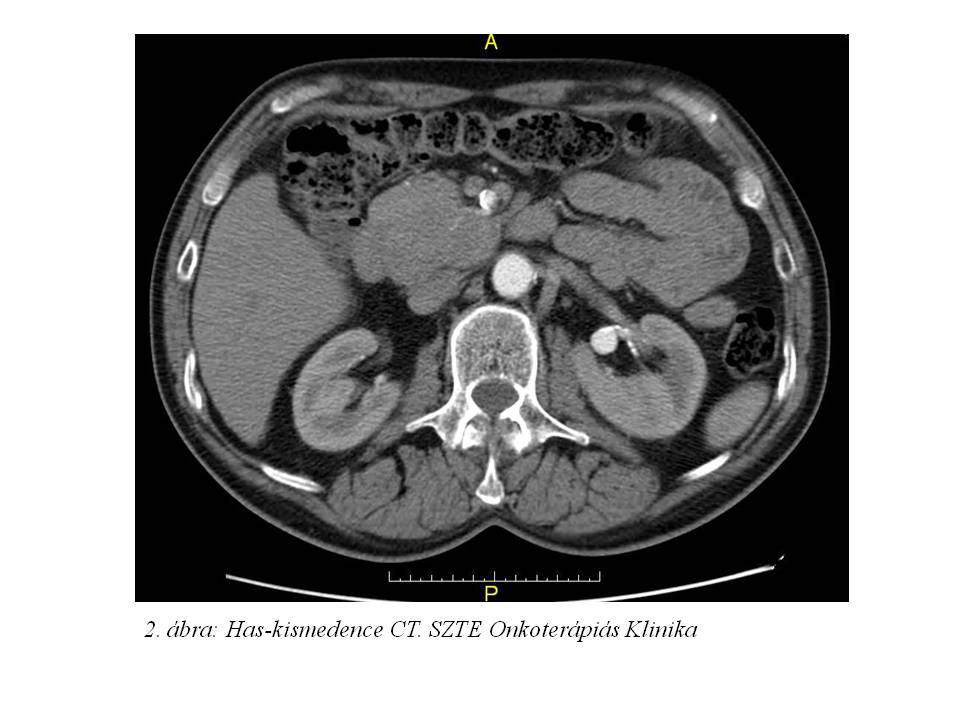

61 éves férfibetegünknél 2013 áprilisában indult kivizsgálás pancreatitisre hasonlító övszerű fájdalom és gyomorürülési zavarok miatt, melyek kb. 3 éve álltak fenn. Hasi UH vizsgálatán (1. ábra) egy nagy retroperitoneális terimét detektáltak, melyet has-kismedence CT vizsgálat (2. ábra) megerősített: a pancreas fej mögött egy 59x51x30 mm-es képlelet detektált, mely a pancreas fejjel összefügg. Mellkas RTG, gasztroszkópia negatív, CA 19-9 normális tartományban volt. UH vezérelt biopszia igazolta jól differenciált neuroendokrin malignus tumorát (immunfentipizálással béta-catein: 1+, KL1: 3+, chromogranin: 3+, synaptophysin: 3+, CD56: 3+, vimentin: -, Ki67: 15%), mely miatt 2013.05.28-án exploratív laparotomia történt az SZTE Sebészeti Klinikán. A folyamat inoperábilisnak bizonyult a környezeti infiltráltság miatt. Anamnéziséből kiemelendő, hogy az elmúlt évben 11 kg-ot fogyott (74 kg-ról 63 kg-ra).